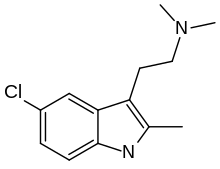

| ST-1936 | artificial | 2-CH3, 5-Cl | CH3 | CH3 | 2-(2-methyl-5-chloro-1H-indol-3-yl)-N,N-dimethylethanamine | 1210-81-7 |